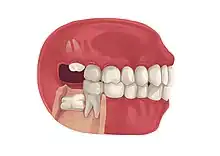

Impacted wisdom teeth are classified by the direction and depth of impaction, the amount of available space for tooth eruption, and the amount of soft tissue or bone (or both) that covers them. The classification structure helps clinicians estimate the risks for impaction, infections and complications associated with wisdom teeth removal.[6] Wisdom teeth are also classified by the presence (or absence) of symptoms and disease.[7]

Impacted wisdom teeth are often described by the direction of their impaction (forward tilting, or mesioangular being the most common), the depth of impaction and the age of the patient as well as other factors such as pre-existing infection or the presence of pathology (cysts, tumors or other disease).[5]:143–144 Each of these factors is used to predict the difficulty (and rate of complications) when removing an impacted tooth, with age being the most reliable predictor[8] rather than the orientation of the impaction.[9]

Impacted wisdom tooth that is tilted forward (mesioangular impaction)